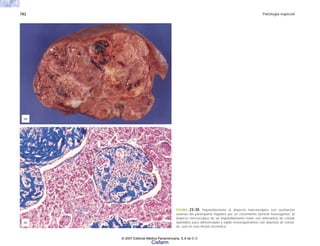

FIGURA 4-7. Cirrosis hepática. a) Aspecto macroscópico del hígado, con sustitución

de su arquitectura normal por múltiples nódulos de regeneración parenquimatosa de

distintos tamaños. b) Los nódulos están separados por bandas irregulares de tejido

fibroso.

(a)

(b)